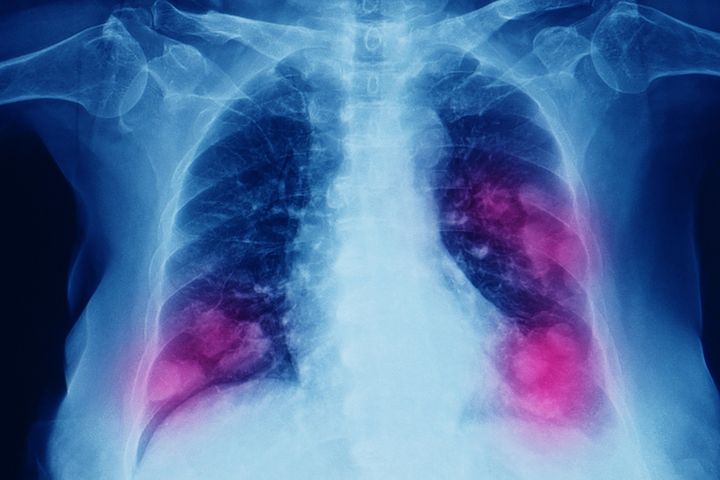

Lung Cancer and Mesothelioma

About lung cancer and mesothelioma

What is lung cancer?

Lung cancer has two major types:

• non-small cell lung cancer (NSCLC), which makes up 85–90% of cases

• small cell lung cancer (SCLC), which accounts for approximately 10–15% of cases.